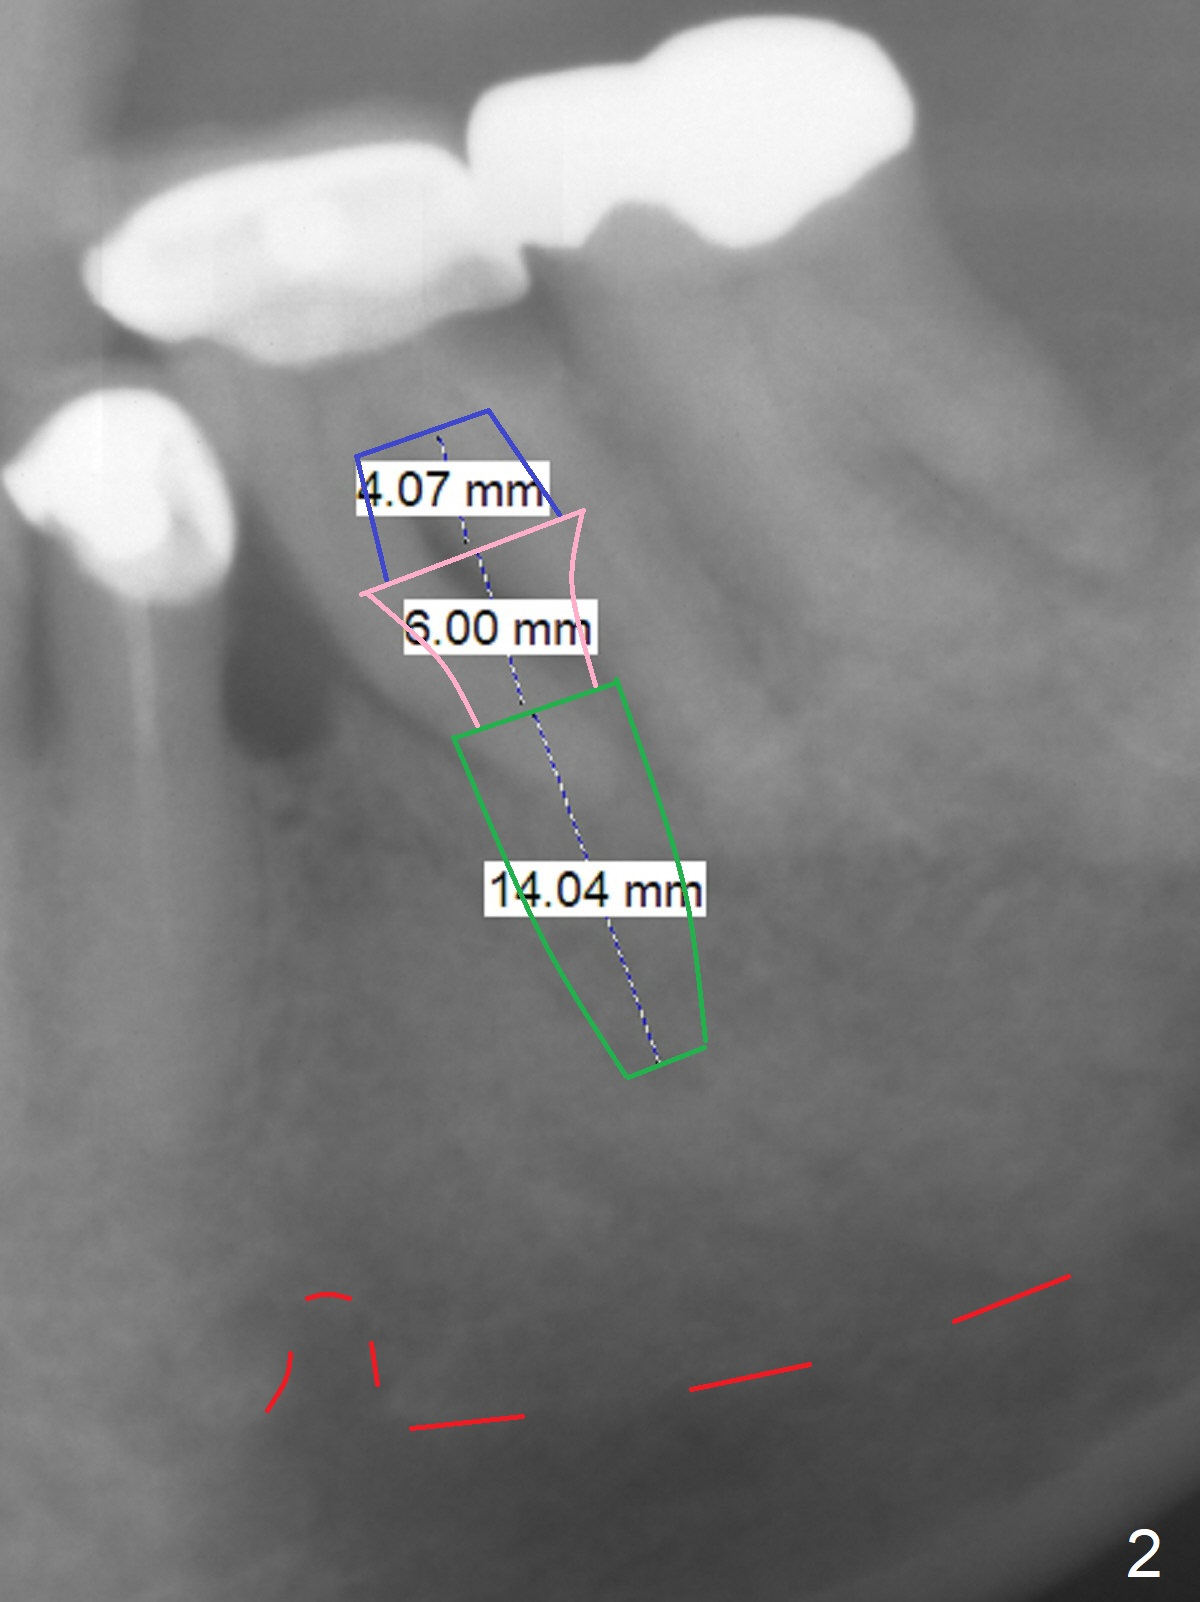

Supraerupted Molar Five months post cementation of #29-31 implant FPD of a 72-year-old man, the supraerupted (Fig.1 arrow) tooth #19 fails (caries (*) and mesial (M) root radiolucency). A 14 mm long implant (Fig.2 green) will be placed deep with 6 mm cuff (pink) and 4 mm abutment (blue). Return to Lower Molar Immediate Implant, Prevent Molar Periimplantitis (Protocols, Table), Armaments, Metronidazole Xin Wei, DDS, PhD, MS 1st edition 06/05/2018, last revision 06/12/2018 |